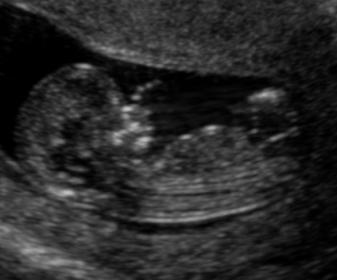

Hi everyone! Here are some scans from my 12w,4d U/S. I'm new to this. Any guesses? :)

Attachment 7012